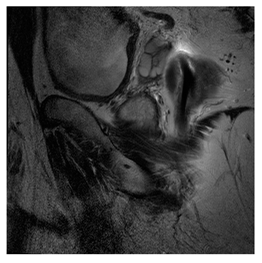

Breast-MRI-NACT-Pilot is an MRI-type image database, collecting breast medical images of 64 patients. Some samples are shown in Figure 12a.

Figure 12.

Sampled images in the tested benchmark databases: (a) Breast-MRI-NACT-Pilot (breast), (b) ACRIN-DSC-MR-Brain (brain), (c) NIH (chest), (d) Lung-PET-CT-Dx (lung), (e) Prostate-MRI (prostate), and (f) Other grayscale standard images.